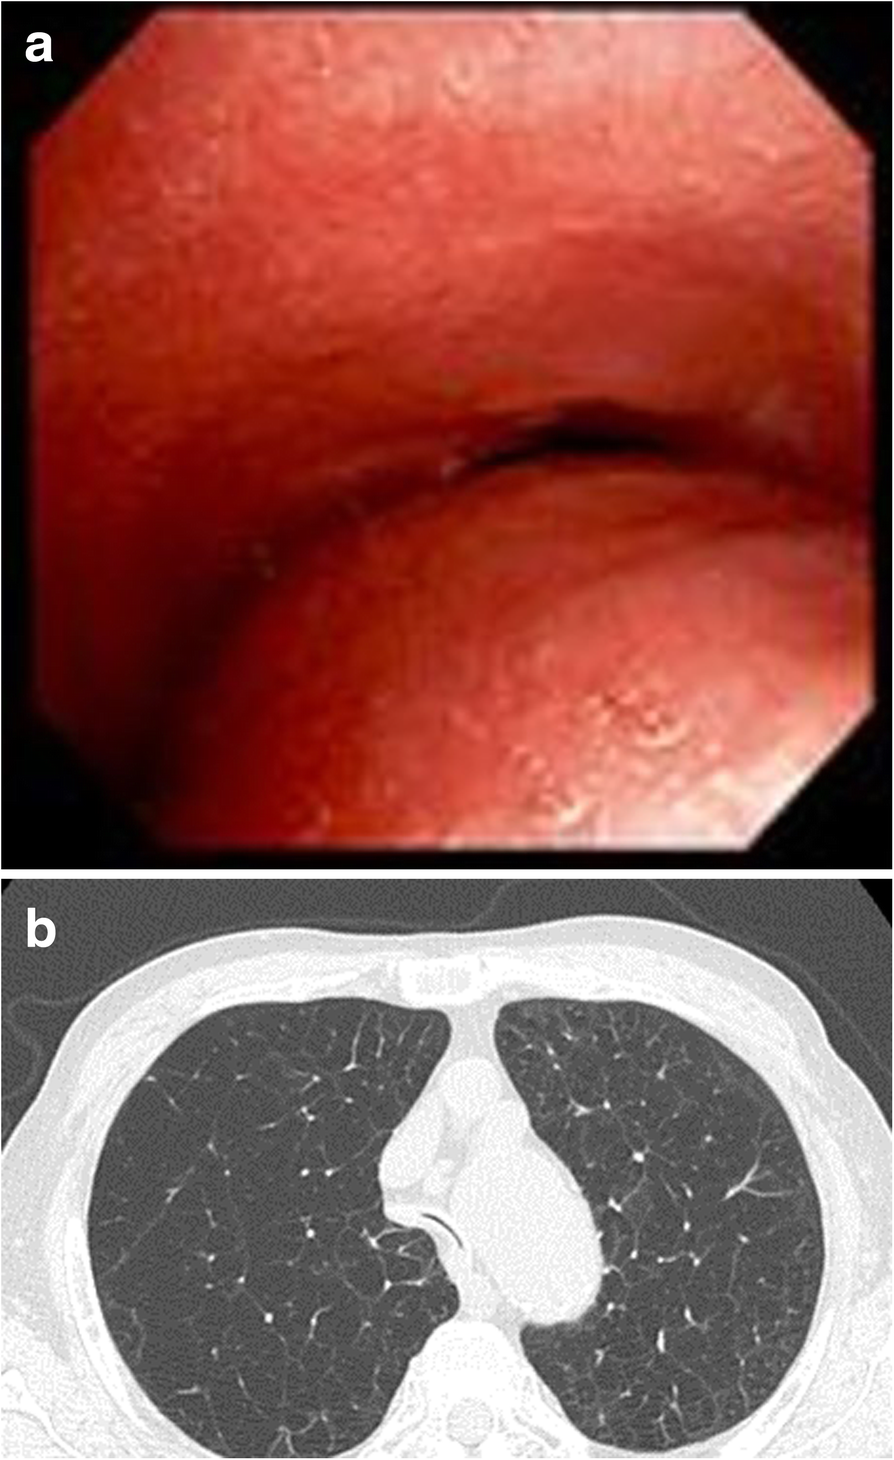

Tracheobronchomalacia Dynamic Airway Evaluation with Multidetector CT AJR Tracheobronchomalacia Icd-10 Importance tracheobronchomalacia (tbm) describes an increased collapsibility of the trachea and bronchi that is greatest on forced expiration. The membrane and supportive tissue at the back of your trachea weaken. Tracheobronchomalacia is the most common congenital tracheal anomaly, affecting 1 in 2100 children. Citation, doi, disclosures and article data. As a result, when you breathe out, this part of the. Tracheobronchomalacia Icd-10.